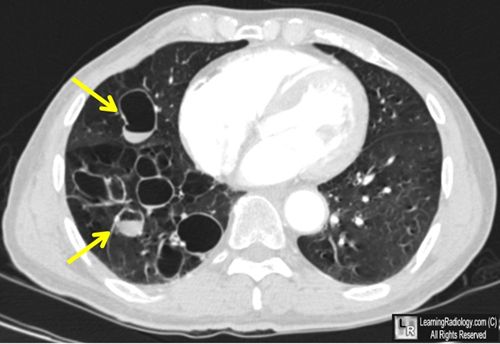

患者47岁,咳嗽咳痰,胸部增强CT如图1所示,什么是最可能的诊断?

2.CT诊断该病,其敏感性和特异性分别为97%、99%

3.CT有印戒征表现:正常情况下,血管径大于相应的支气管。在支气管扩张时,支气管径大于相应的血管

4.“ 轨道征”或“ 蜂窝征”代表支气管扩张,及管壁增厚